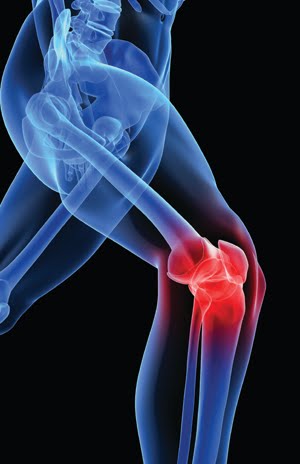

Joint Replacement

Rothman Orthopaedics' Joint Replacement Program is one of the nation's top joint replacement centers, performing more than 17,000 joint surgeries annually.

The joint replacement team at Rothman Orthopaedic Institute performs more than 9,000 surgeries every year. Each member of the team is specially trained, has extensive experience and is skilled to perform total joint replacements. Every physician that is a part of this outstanding team of doctors has undergone extensive subspecialty training during his/her residency and fellowship. This team is at the cutting edge of new research in the joint replacement field and Rothman physicians are actually responsible for training other orthopaedic surgeons through international lectures, webcasts, and surgical satellite simulcasts.

If you experience pain in any of your joints due to physical activities such as walking, running, and climbing stairs, it may be time to have a Rothman Orthopaedic Institute specialists diagnose your case. Joint replacement may be the answer for you. When simply sitting in a favorite chair or sleeping in your bed causes enough pain to wake you or make your life extremely uncomfortable, joint replacement may be able to get you back to an active lifestyle with less pain.